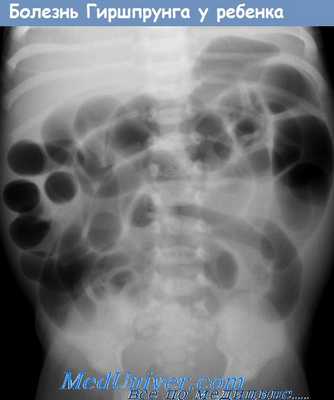

а - Обзорная рентгенограмма брюшной полости взрослого с недавно диагностированной болезнью Гиршспрунга.

Прямая кишка (показана стрелкой) значительно расширена.

(а) На обзорной рентгенограмме органов брюшной полости, выполненной в положении стоя, отмечается тень фекалий, заполняющих почти всю брюшную полость с выпячиванием контуров брюшной полости.

(б, в) Заметна выраженная дилатация сигмовидной кишки (С), занимающей пространство от верхней части брюшной полости до таза.